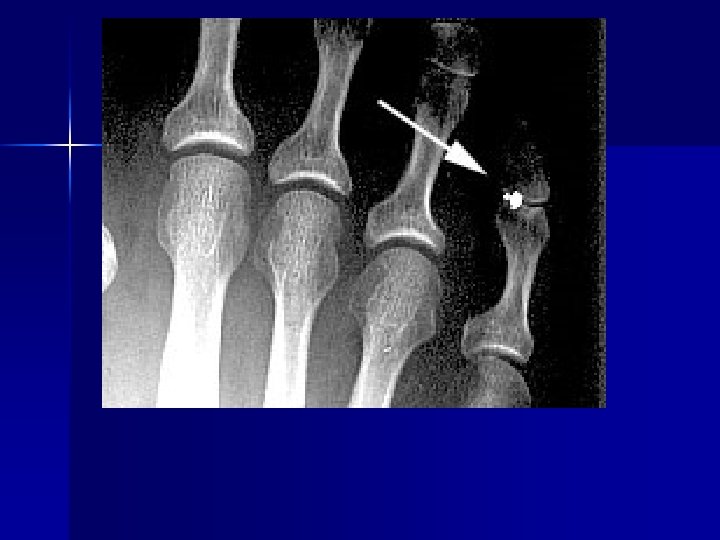

PATHOLOGY NOT ARTIFACT

Name & cause of this?

Evaluating Images What do you think?

n n n Does this show good detail? Is all of the anatomy present? How is the density / contrast?